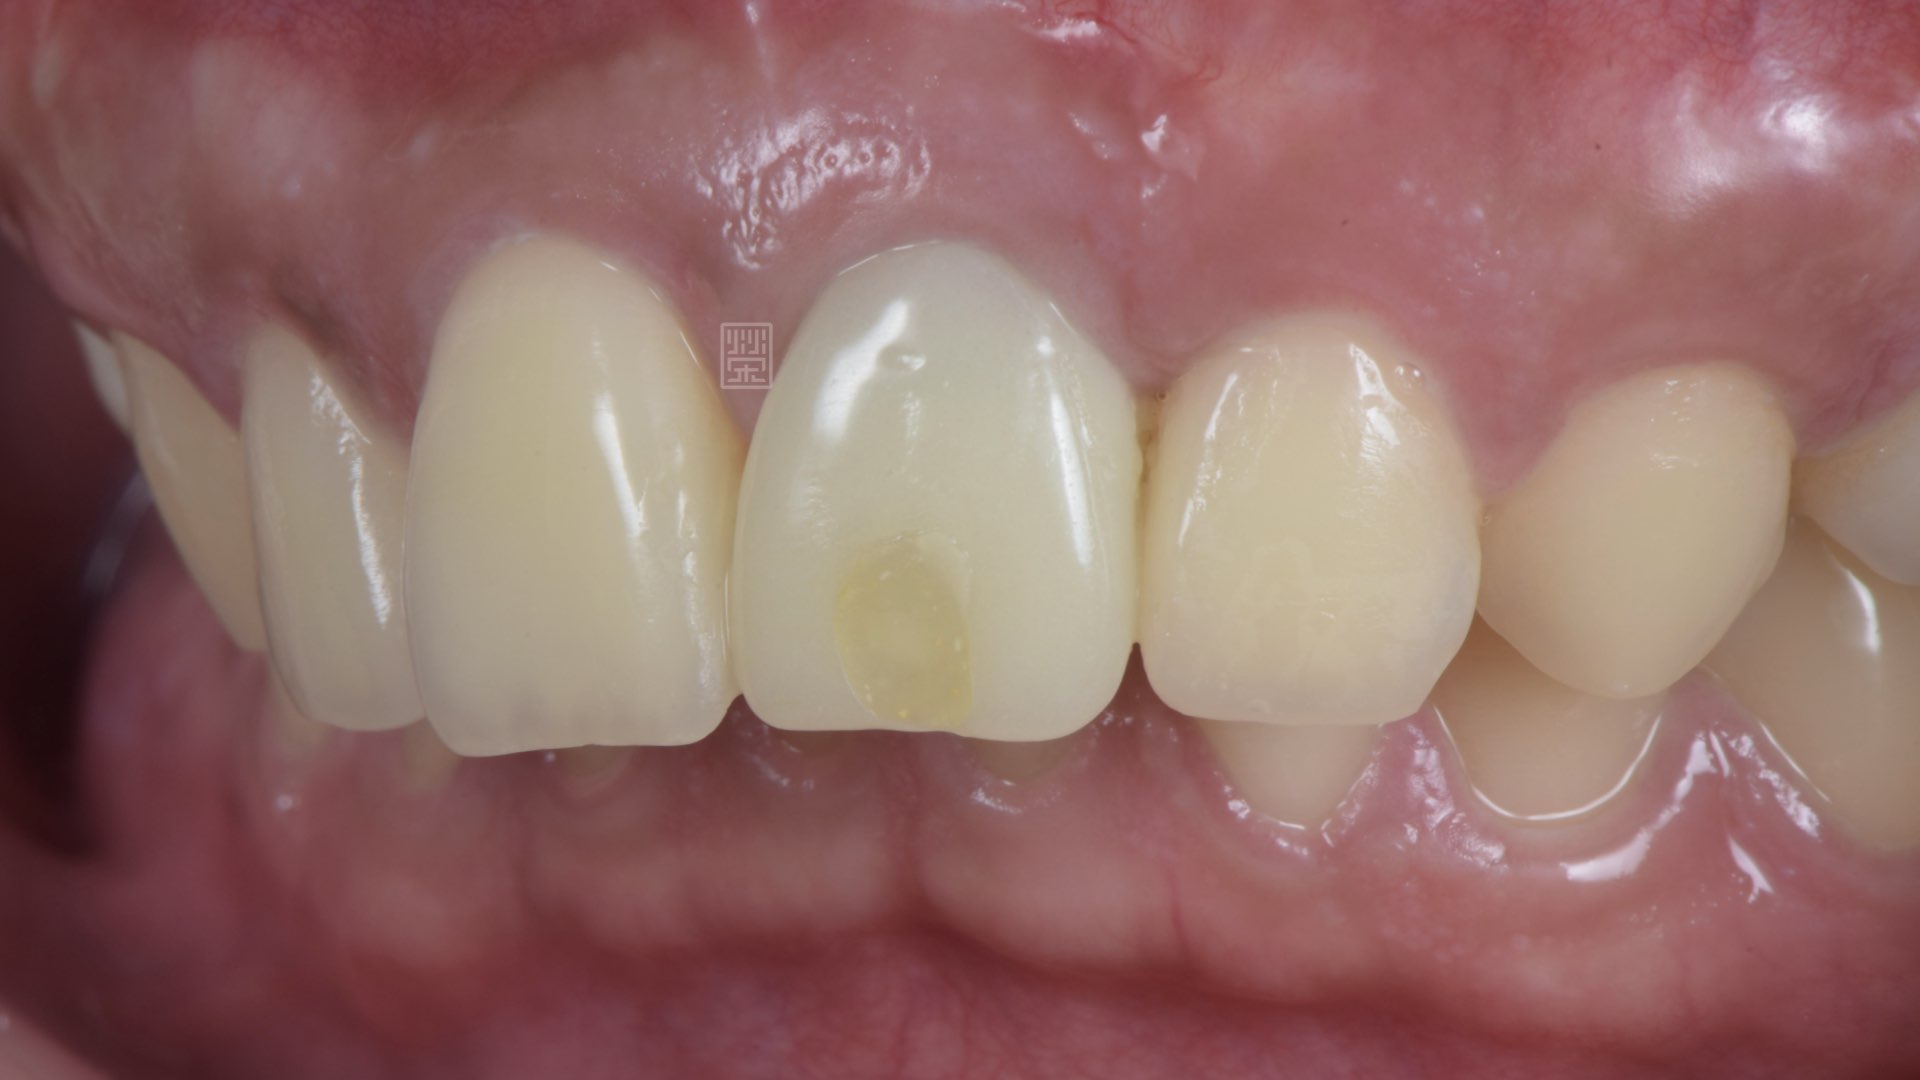

植牙臨時假牙

植牙全瓷冠